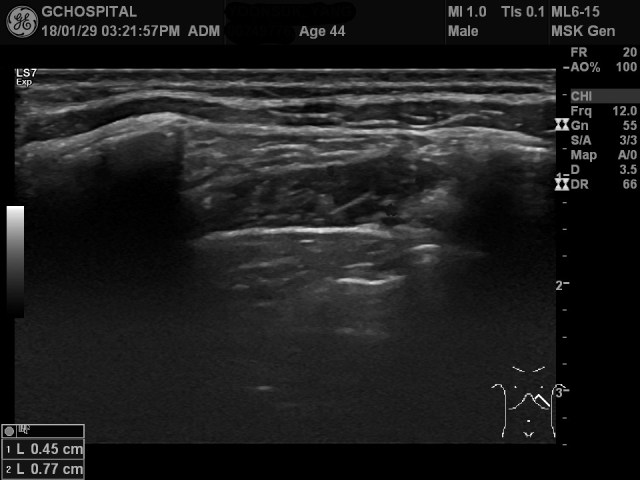

위의 영상은 44세 남자환자가 운전 중 교통사고로 인해 왼쪽 가슴쪼에 통증을 느껴서, 갈비뼈 골절의 가능성을 확인하기 위해 시행했던 초음파영상입니다. 늑간근의 외층에는 별다른 이상소견이 없지만, 내층에는 국소적인 변화가 보입니다.

늑간근의 내층 중에서 아랫쪽 늑골과 인접한 부위의 에코가 주변보다 더 낮으면서 주변보다 근육 내부의 근섬유들 사이의 구분이 깨져있습니다.